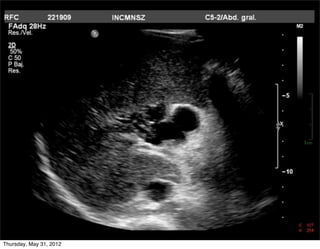

Porta principal

• Unión de esplénica y

mesentérica sup

• Orden (post a ant)

•     Porta-Colédoco-Arteria

• Diámetro 11 +/- 2 mm

• Visibles por colágena

incich/grupo ct scanner                      Departamento de Radiología/Unidad PET-CT